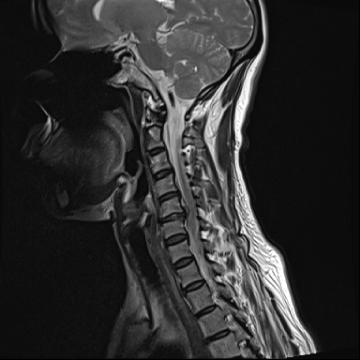

목디스크

척추뼈 사이사이에 무게와 충격을 흡수할 수 있는 연골조직을 디스크, 즉 경추 추간판이라 합니다.

목의 무리한 사용이나 잘못된 자세, 퇴행성 변화 등으로 인해 디스크 안에 있는 수핵이 밖으로 탈출하게 되어 신경을 누르는 경추 추간판 탈출증을 목 디스크라 합니다.

질환을 의심해 볼 수 있는 자가진단법으로 정확한 진단은 MRI와 같은 영상학적 검사를 필요로 합니다.

목디스크 치료법

목디스크가 심각하지 않은 경우에는, 신경 유착을 제거해 주는

신경성형술, 고주파를 쏘아 튀어나온 디스크와 염증을 가라앉히는

고주파 수핵성형술과 같은 비수술 치료를 통해 완화가 가능합니다.

비수술적 치료 효과가 없거나 디스크의 신경 압박이 심한 경우는

미세현미경수술, 인공디스크 치환술, 경추유합술을 통해 치료가 가능합니다.